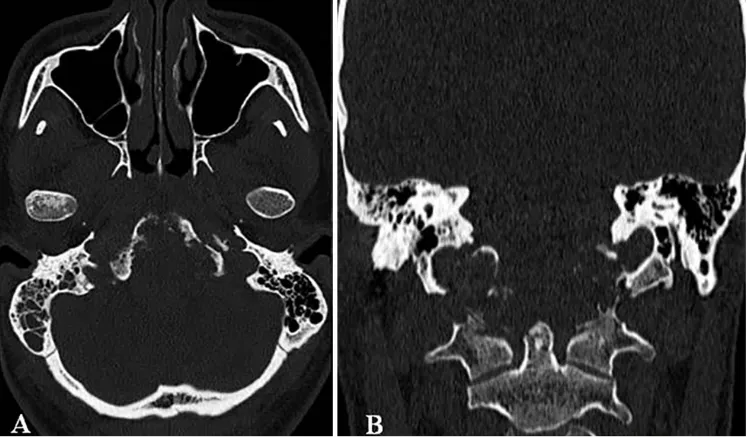

在植入螺钉后,福教授还使用Roy-Camille技术将颈椎的C0-C5椎体进行融合,使用聚甲基丙烯酸甲酯(Polymethyl Methacrylate)材料填充椎体之间的空隙,以促进骨组织的生长和愈合,从而提升颈椎的稳定性。

术后的效果也如福教授所料,经过PMMA材料枕髁重建的部位稳定牢固,形态恢复良好。三维CT也显示杰森C0-C3-C4-C5枕颈融合稳定,螺钉的弯曲设计也有助于后续质子治疗的开展。